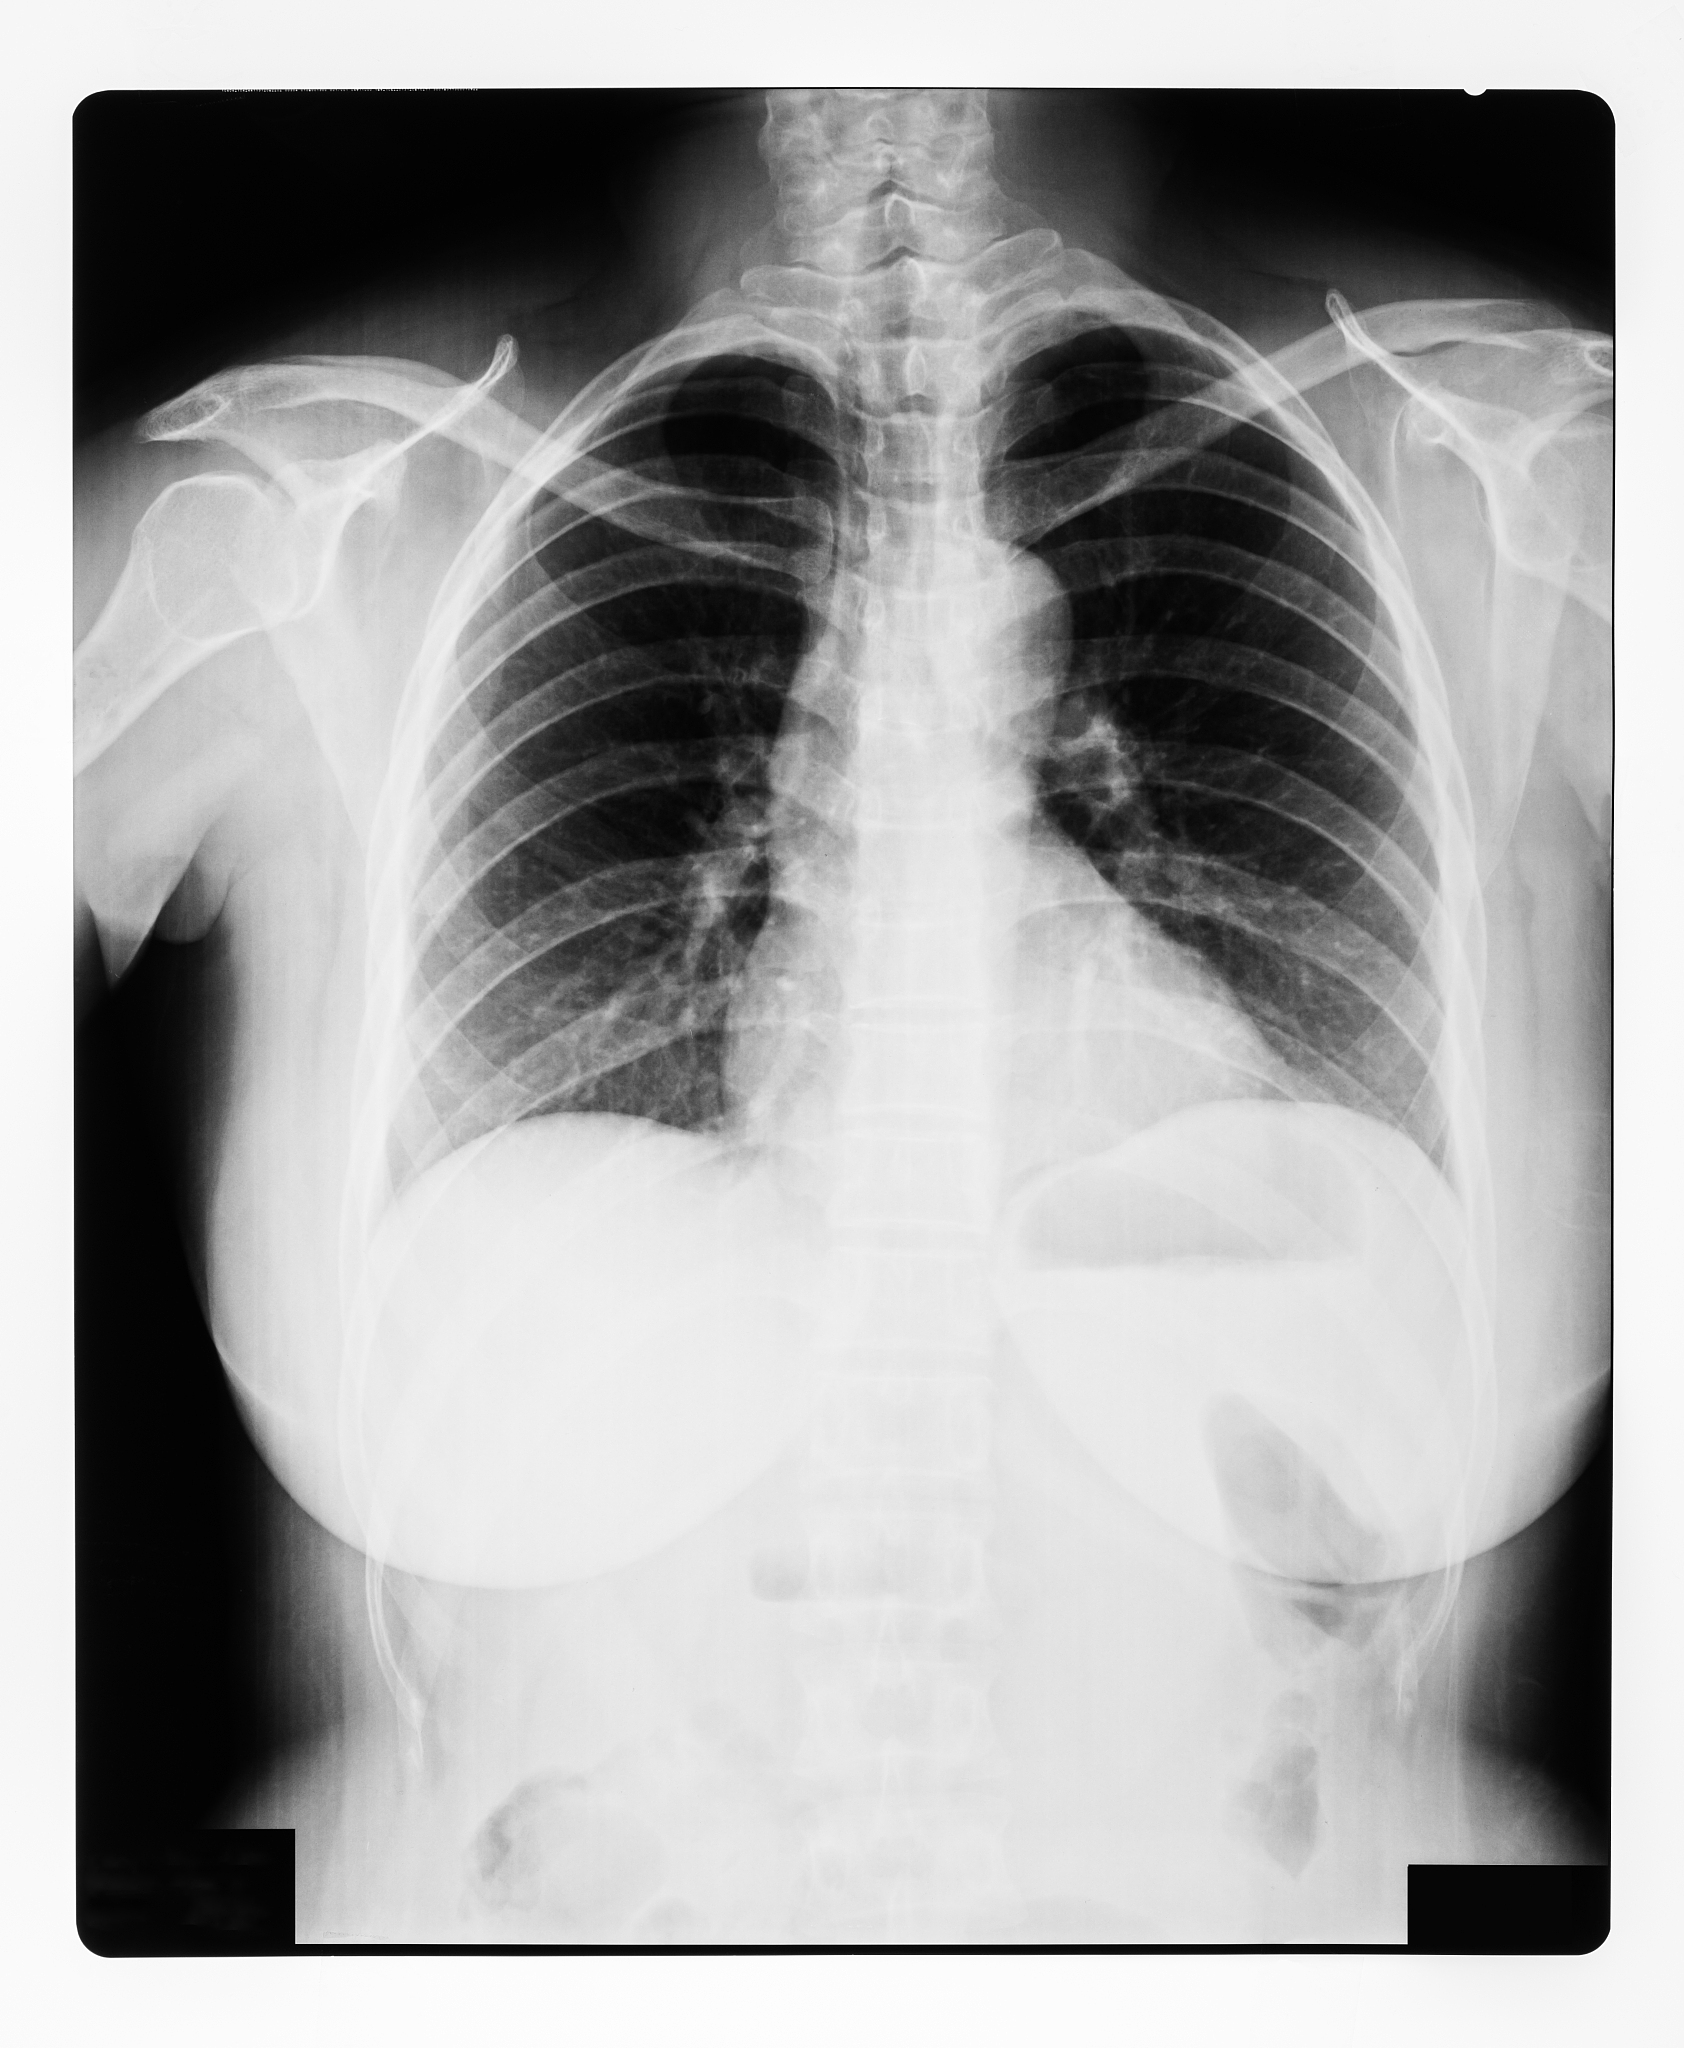

慢性阻塞性肺病(COPD)是一种常见的慢性呼吸系统疾病,患者常合并急性下呼吸道感染,导致病情加重,影响生活质量。本文将介绍COPD合并急性下呼吸道感染的护理问题及对策,帮助患者及家属更好地应对疾病。

1. 呼吸困难: 感染加重气道炎症和阻塞,导致呼吸困难加剧。2. 气道感染: 细菌或病毒感染引起咳嗽、咳痰加重,痰液颜色和性状改变。3. 咳嗽、咳痰: 气道分泌物增多,患者咳嗽加剧,难以有效咳痰,影响呼吸道通畅。4. 氧合不足: 气流受限和感染导致氧合功能下降,出现呼吸急促、心率加快、口唇发绀等症状。5. 营养不良: 呼吸困难和疾病状态影响食欲和消化功能,导致营养摄入不足。6. 心理问题: 疾病反复发作和症状加重易导致患者焦虑、抑郁等心理问题。